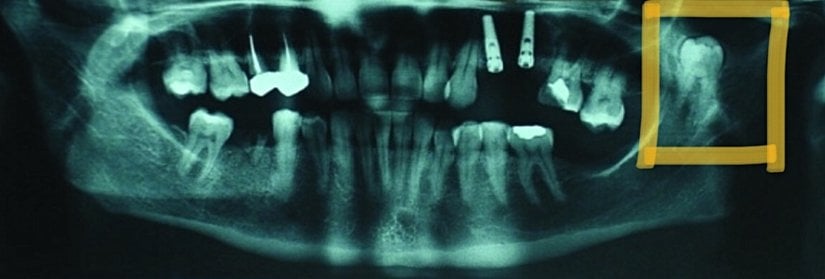

Yukarıda görülen vakada ise maxiller sinüste süren bir 20 yaş dişi görüyoruz. Sol üst 20 yaş dişi olması gereken yerde sürmek yerine, kafa boşluklarımızdan olan maxiller sinüste sürmeye karar vermiş olmalı. Sağ 20 yaş dişi doğru pozisyonunda sürerken, sol taraftaki diş hem yanlış yerde sürmüş hem de yine kendisi gibi oldukça kalsifiye bir yapıya eşlik etmekte.

Dişin morfolojisinin de normalden oldukça sapmış olduğunu izlediğimiz bu vakada hasta, yanağına yayılan yoğun ağrı ile uzun süre vakit geçirmiş ve ağrının başlamasından ancak 1 yıl sonra kaynağın bu diş olduğu anlaşılmıştır.